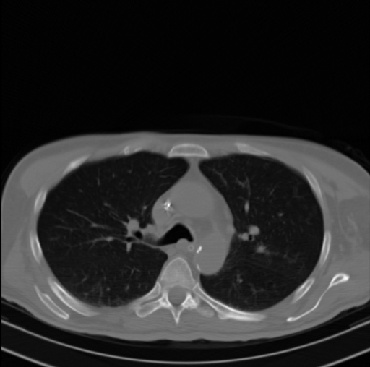

Early and reliable COVID-19 diagnosis based on chest 3-D CT scans can assist medical specialists in vital circumstances. Deep learning methodologies constitute a main approach for chest CT scan analysis and disease prediction. However, large annotated databases are necessary for developing deep learning models that are able to provide COVID-19 diagnosis across various medical environments in different countries. Due to privacy issues, publicly available COVID-19 CT datasets are highly difficult to obtain, which hinders the research and development of AI-enabled diagnosis methods of COVID-19 based on CT scans. In this paper we present the COV19-CT-DB database which is annotated for COVID-19, consisting of about 5,000 3-D CT scans, We have split the database in training, validation and test datasets. The former two datasets can be used for training and validation of machine learning models, while the latter will be used for evaluation of the developed models. We also present a deep learning approach, based on a CNN-RNN network and report its performance on the COVID19-CT-DB database.